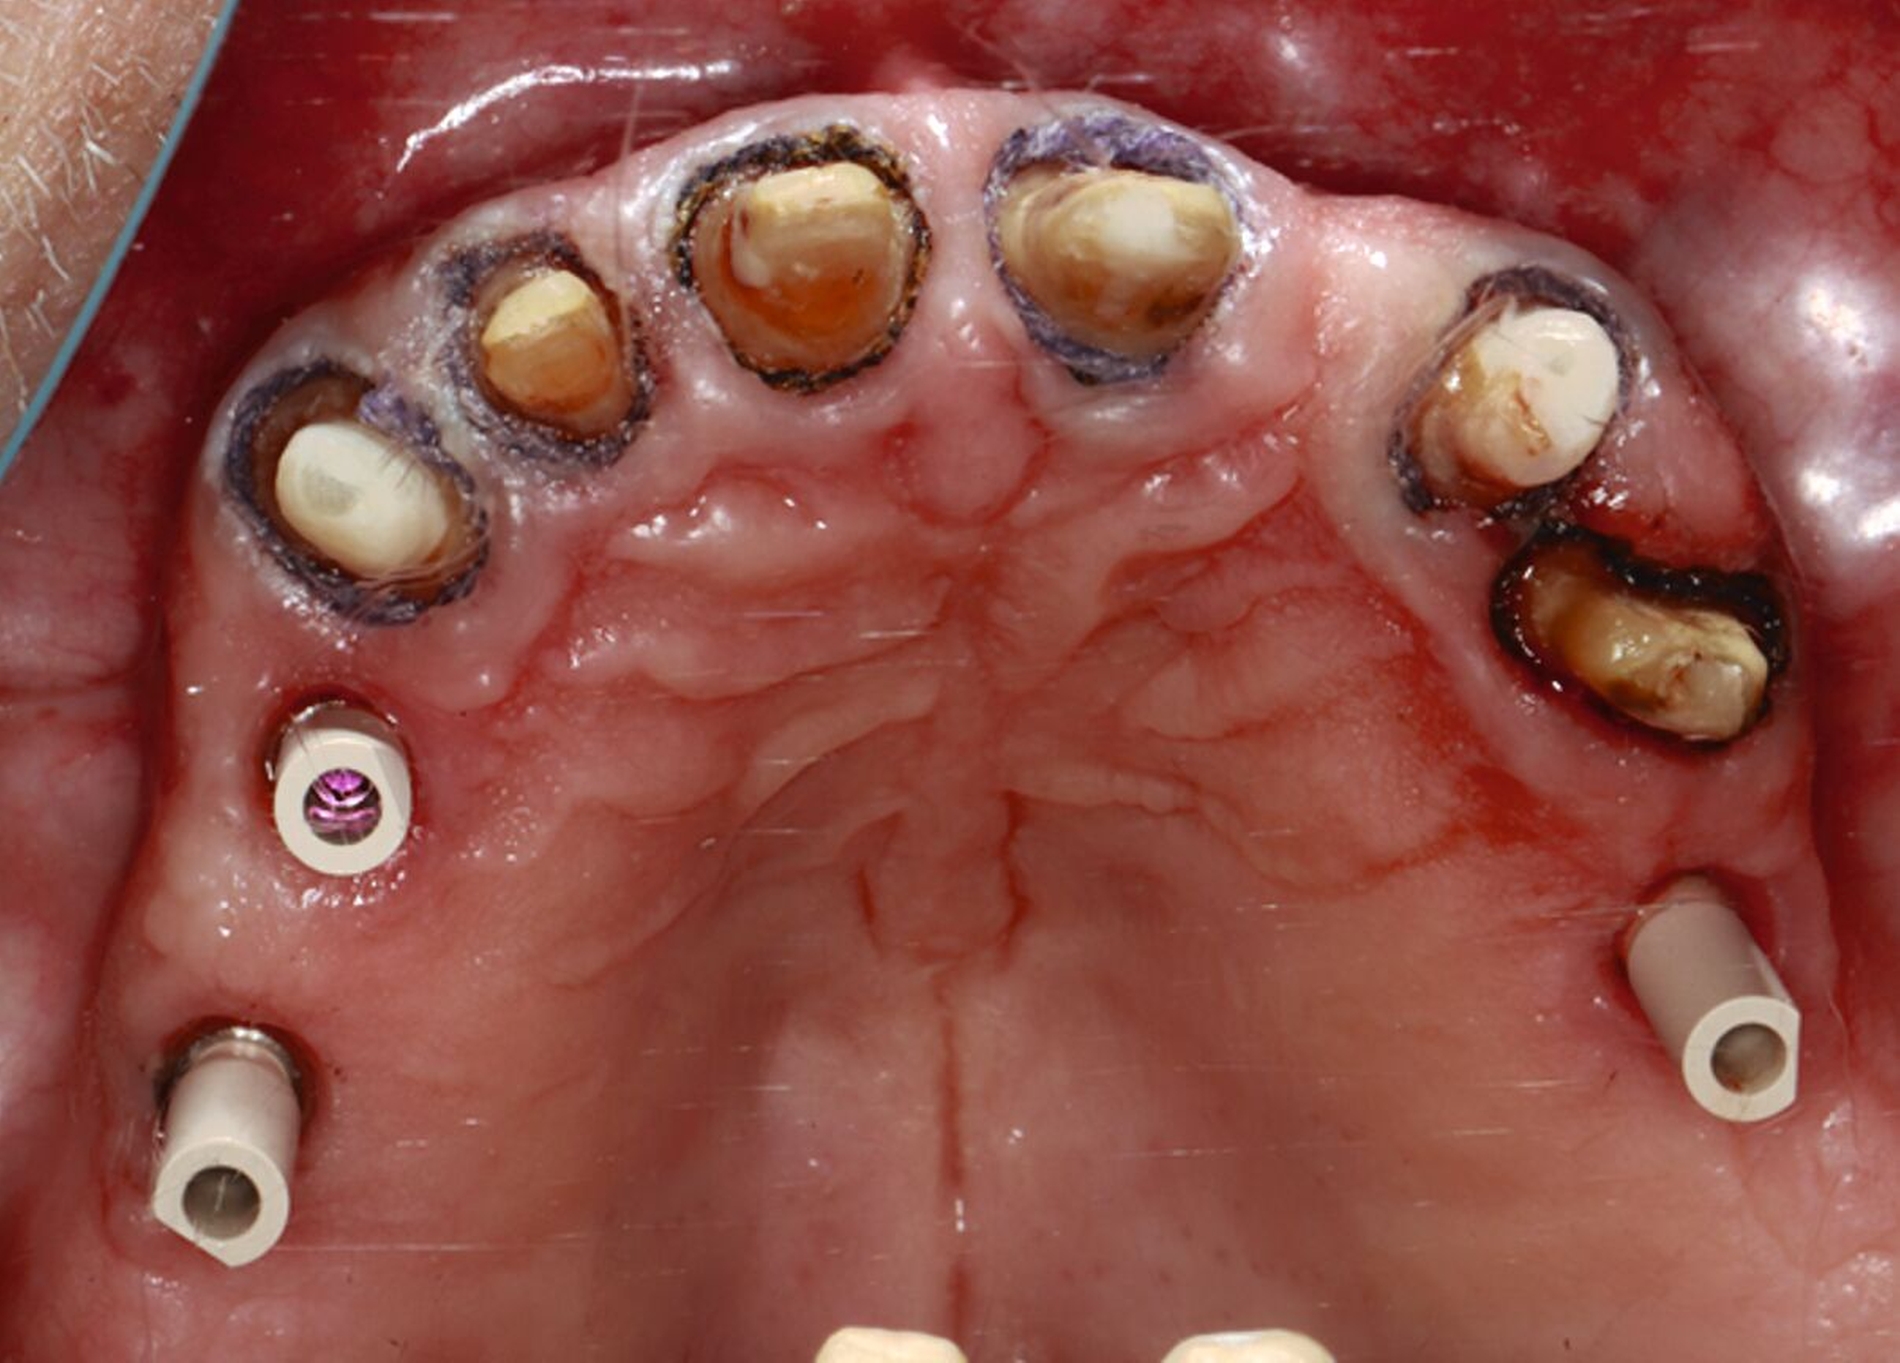

Die Stümpfe wurden folglich zur Aufnahme von Teleskopkronen präpariert und mittels Doppel-Fadentechnik für die konventionelle Abformung mit dem Polyether vorbereitet. Nachdem das zahntechnische Labor die NEM-Primärteleskope hergestellt hatte, wurden sie am Patienten anprobiert und mit einem Tropfen provisorischen Zements auf den Stümpfen fixiert (Abbildung 5a), um sie anschließend in der Fixationsabformung mit abzuformen (Abbildung 5b).

Nach Durchführung einer dentalen Volumentomografie (DVT) wurden daher zahnärztliche Implantate in Regio 14, 15 und 25 im Sinne einer verkürzten Zahnreihe geplant und inseriert (Abbildung 7). Nach dreimonatiger subgingivaler, konventioneller Einheilzeit wurden die Implantate freigelegt. Zwei Wochen später begann man die vorhandenen Primärkronen zu entfernen. Die Stümpfe wurden nachpräpariert und es wurden erneut Fäden gelegt (Abbildung 8a und 8b).

Nachdem die Einheilkäppchen entfernt und die Scanbodies in die Implantate eingeschraubt wurden, erfolgte der Intraoralscan (Abbildung 8c). Der festsitzende Zahnersatz wurde im zahntechnischen Labor designt und aus monolithischem Zirkonoxid gefräst. Die Kronen konnten schließlich selbstadhäsiv auf den Stümpfen befestigt werden. Das Einschrauben der Implantatkronen erfolgte mit Drehmomentschlüssel auf 35 Ncm nach Herstellerangabe. Die Schraubkanäle wurden anschließend verschlossen. Mit dem Endergebnis (Abbildung 8d) zeigte sich der Patient auch im Recallverlauf hochzufrieden.